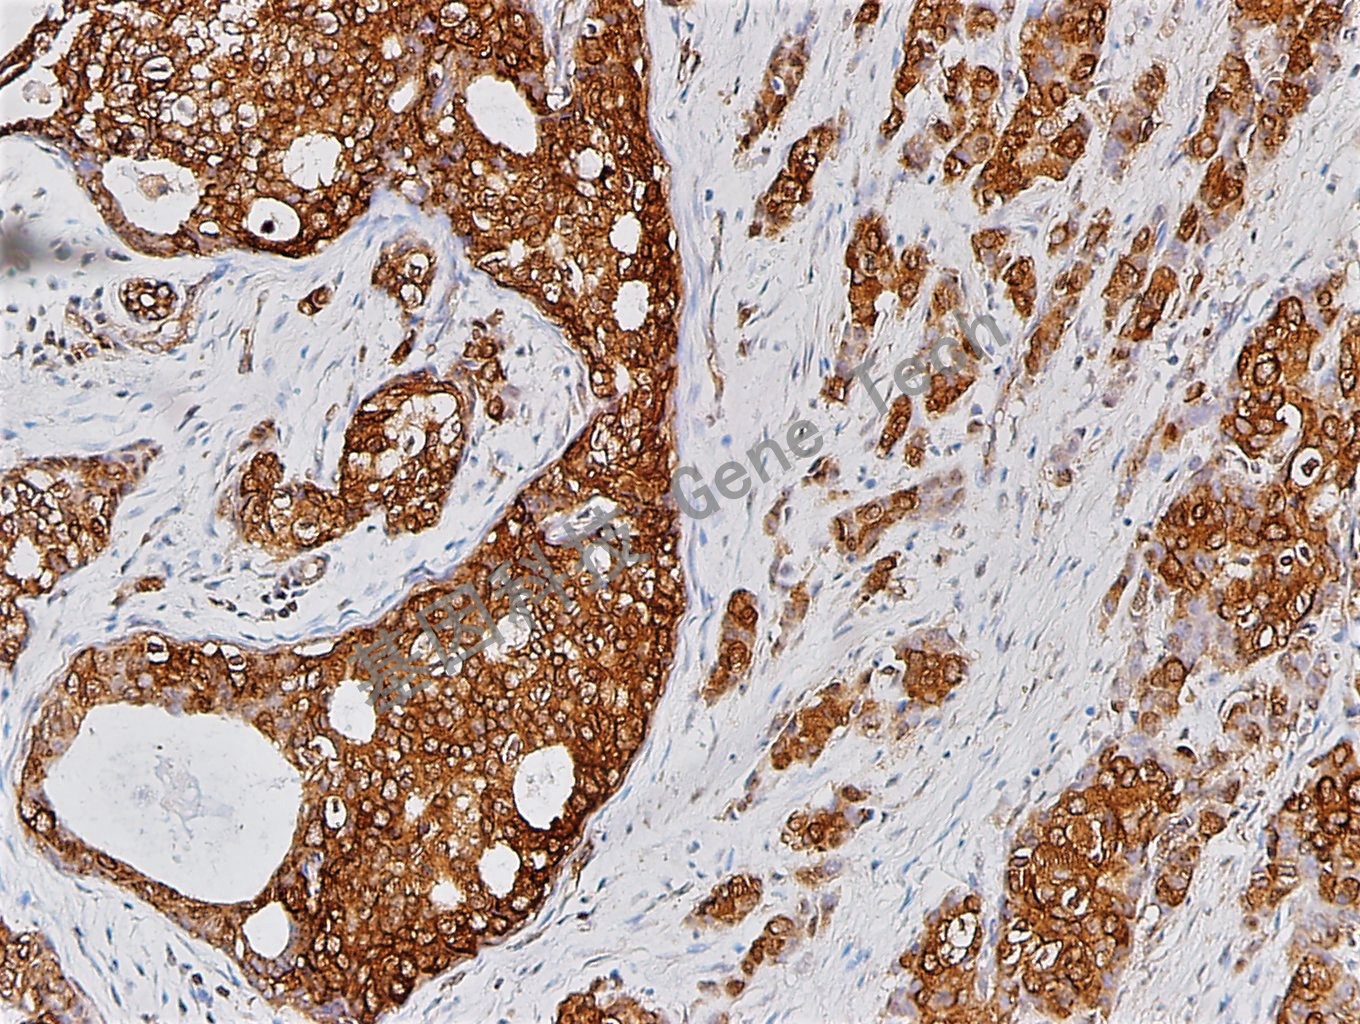

| 預(yù)處理:高pH熱修復 | 陽性部位:細胞漿 | 陽性對照:乳腺癌 |

| 乳腺癌石蠟切片,用 nm23(GT2026)染色,細胞漿陽性,DAB 顯色。 | ||